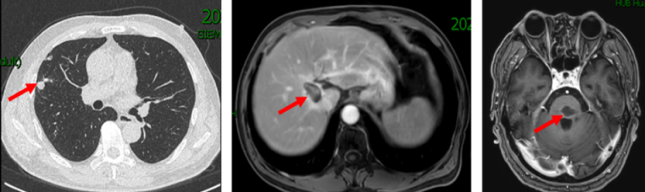

2019年3月胸部CT:右肺上叶近水平裂胸膜处有一枚结节,大小约6mm*5mm,考虑肿瘤转移;腹部MRI:肝右叶S8段新发结节,弥散受限,约16mm*12mm,考虑转移瘤可能性大。

2019.10.18 当地医院头部MRI示:脑干区异常信号,约11mm*15mm,考虑转移瘤合并脑卒中。

脑部蛋氨酸PET示:脑桥结节,蛋氨酸代谢异常增高,SUVmax 4.51,考虑转移性恶性肿瘤。

影像科、神经内科会诊,考虑脑部病灶为肠癌转移病灶。